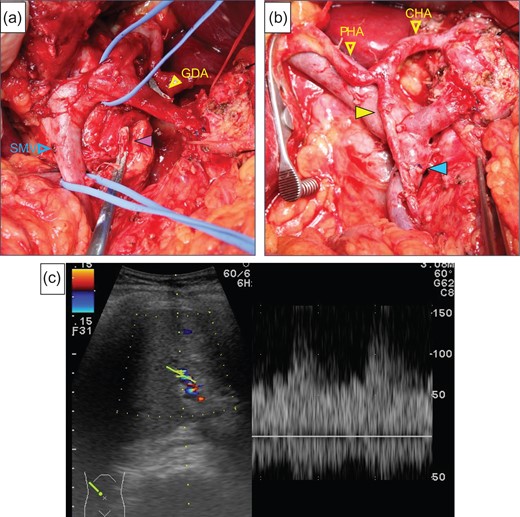

After laparotomy we identified the MAL, which had compressed the origin of the CA (Fig. 2a), and Doppler ultrasonography showed that the hepatic arterial flow was hepatopetal, but the common hepatic arterial flow was hepatofugal (no record available). First, the MAL was divided (Fig. 2b). After clamping the GDA (Fig. 2c), the hepatic arterial flow was not satisfactory (Fig. 2d). We continued the operation under GDA clamping. Finally, the specimen was connected only by the IPDA, SMV and GDA. The IPDA and aneurysm were ligated and divided (Fig. 3a). At this time, 92 min after clamping the GDA, however, the hepatic arterial flow was not improved. We were able to preserve the GDA 10 mm from its root, we divided the GDA and SMV and extracted the specimen. Arterial reconstruction by end-to-end anastomosis of the GDA and MCA was performed by plastic surgeons (Fig. 3b). After reconstruction, the hepatic arterial signal was improved (Fig. 3c).

(a) The purple arrow indicates the stump of the aneurysm. (b) The image was after reconstruction by end-to-end anastomosis of the GDA and the MCA (yellow arrow). The blue arrow indicates the anastomotic part of the SMV. (c) We checked the hepatic arterial flow after reconstruction, the hepatic arterial signal had increased.